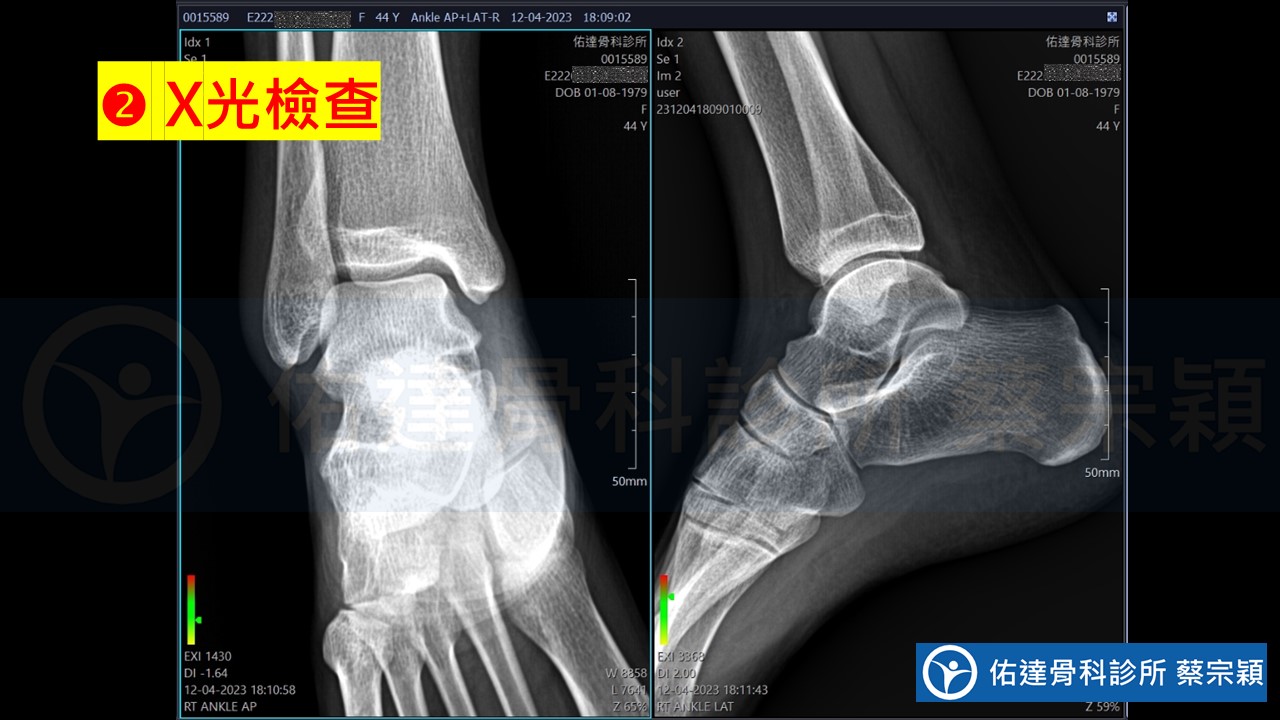

骰骨症候群、骰骨錯位症候群、骰骨脫位錯位、骰骨卡住、Cuboid syndrome、Cuboid subluxation、Locked cuboid:治療流程分享